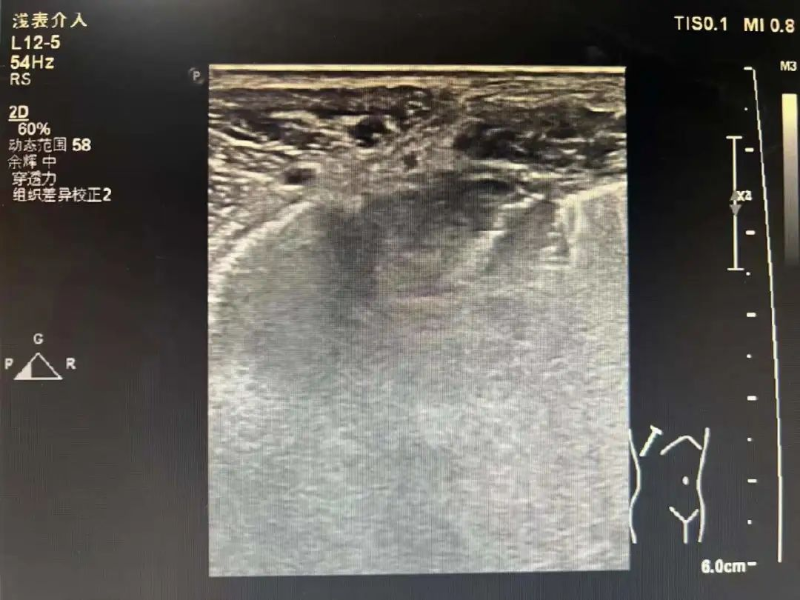

無獨有偶,3月16日,林伯伯(化名)四天前開始出現陣發性雙側胸痛,并伴有咳嗽、咳痰,遂到我院就診。門診檢查胸部增強CT顯示右肺上葉占位,疑是原發性支氣管肺癌,收治入院。

為進一步診斷病情,3月17日在陳勇輝超聲引導下,超聲醫學科蔣朝霞主任醫師為林伯伯進行肺腫瘤穿刺活檢。超聲引導下以右肺腫瘤最清楚處為目標,用穿刺針沿著引導線刺入,通過針尖穿越腫瘤觸發活檢槍進行活檢。穿刺后,林伯伯無不適。我院超聲醫學科成功完成穿刺活檢,為患者進行專科治療做“最強輔助”,充分體現了我院超聲醫學科能力水平的綜合提升,讓患者能就近就醫、就近診斷,為患者減輕看病就醫經濟負擔和解決奔波勞碌的問題。